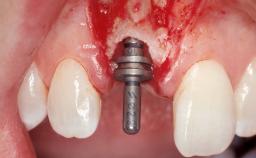

Late Flapless Placement of an Implant in a Maxillary Left Central Incisor Site

A 39-year-old male patient presented with a chief complaint of discomfort and gingival discoloration around his maxillary left central incisor. He was in good general health and was a non-smoker. His past dental history was significant because of the traumatic fracture of tooth 21 in a sporting accident at age 13. Initial dental treatment included endodontic therapy and a full-coverage restoration. The patient became symptomatic 5 years later, when structural failure of the tooth resulted in the dislodgment of the crown. Endodontic retreatment, apical surgery, and post-and-core restoration were performed.

Bone Augmentation Horizontal|Staged

Augmentation Materials Xenogenous|Membrane

Soft Tissue Grafting Simultaneous